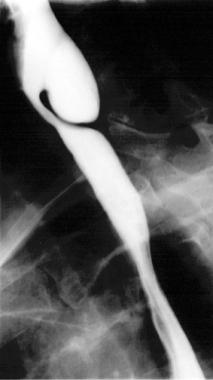

Diverticule de Zenker Diverticule pharyngé-oesophagien

Le diverticule pharyngo-oesophagien, appelé diverticule de Zenker, est une poche entre le pharynx et l’oesophage, faisant hernie au niveau de la partie basse et interne du cou.